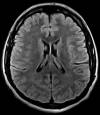

En nuestros centros se realizan estudios y diagnósticos de resonancia magnética musculo-esquelética

de Resonancia ,Magnética Musculo-Esquelética, de la marca italiana Esaote, es único en su diseño ya que nos permite realizar exámenes en bipedestación (el paciente estará de pie, para que se tenga otra perspectiva del comportamiento del cuerpo durante el examen).